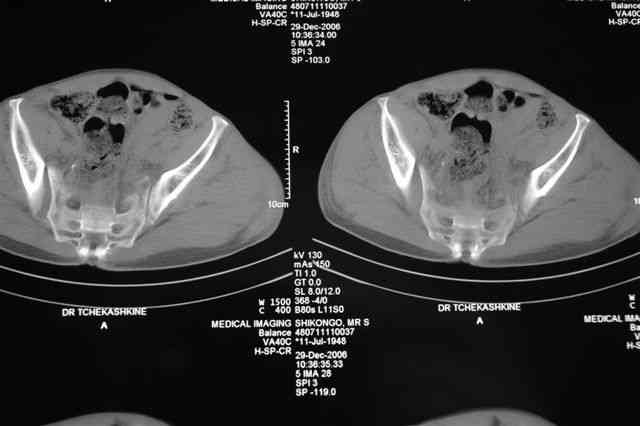

По-поводу фиксации таза спонгиозными винтами. Данный способ все-таки показан для фиксации повреждения крестцово-подвздошного сочленения или переломов крестца. Мне кажется, что в данной случае ситуация иная - имеется перелом "основания" крыла подвздошной кости (в который вовлечена и поверхность, составляющая крестцово-подвздошное сочленение). Не уверен, что фиксация данного повреждения (и заднего полукольца) винтами будет стабильной, так как именно на уровне 1-2 крестцовых позвонков (где обычно вводят винты) линия перелома уходит в латеральном направлении от крестцово-подвздошного сочленения.

По-поводу репозиции костей таза. Производить репозицию костей все-таки необходимо. Пока я не встретил информации, сколько времени прошло с момента травмы, но одномоментно низвести правую половину таза может быть тяжело, учитывая и наличие перелома бедренной кости (что затруднит тракцию за нижние конечности).

Я просмотрел томограммы и у меня создалось впечатление, что винтам есть за что *зацепиться*. В сочетании с 5 мм Шанц винтами, проведенными через нижне-переднюю ость спереди назад через КП сочленения -стабильность тазового кольца должна восстановиться. - Это , конечно, при условии , что закрытая рнепозиция будет успешной.

PI>По-поводу репозиции костей таза. Производить репозицию костей все-таки необходимо. Пока я не встретил информации, сколько времени прошло с момента травмы, но одномоментно низвести правую половину таза может быть тяжело, учитывая и наличие перелома бедренной кости (что затруднит тракцию за нижние конечности).

Травма произошла 22 или 23 декабря, ко мне больной попал 26 декабря, 3 января -остеосинтез перелома бедра и внутр.лодыжки.

Да, я рассматривал и этот вариант контрлатеральной тяги в аппарате таз-бедро с целью устранения вертикального смещения правой половины таза, но

после КТ отказался от этой идеи - двусторонний перелом крестца в зоне 1 - алярная часть, при попытке низведения правого гемипелвиса теоретически есть вероятность смещения

фрагмента крестца слева.